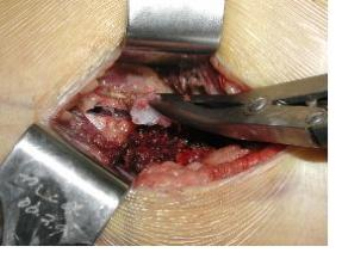

절개 생검(incisional biopsy)시에는 정확한 생검 부위를 선택하며, 충분한 양의 조직을 채취하고, 부위에 따라 종양의 분화도가 다를 수 있으므로 필요에 따라 2-3개 장소에서 채취합니다.

[ 절개 생검 ]